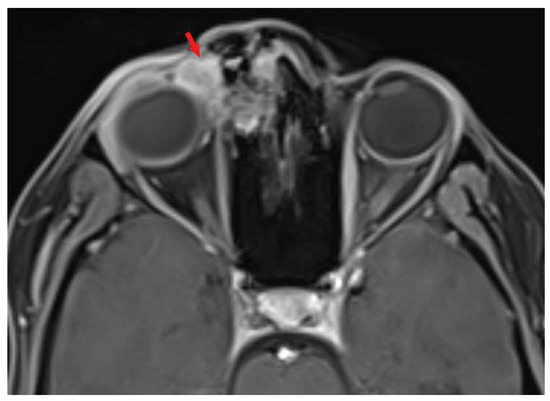

2. Case Presentation